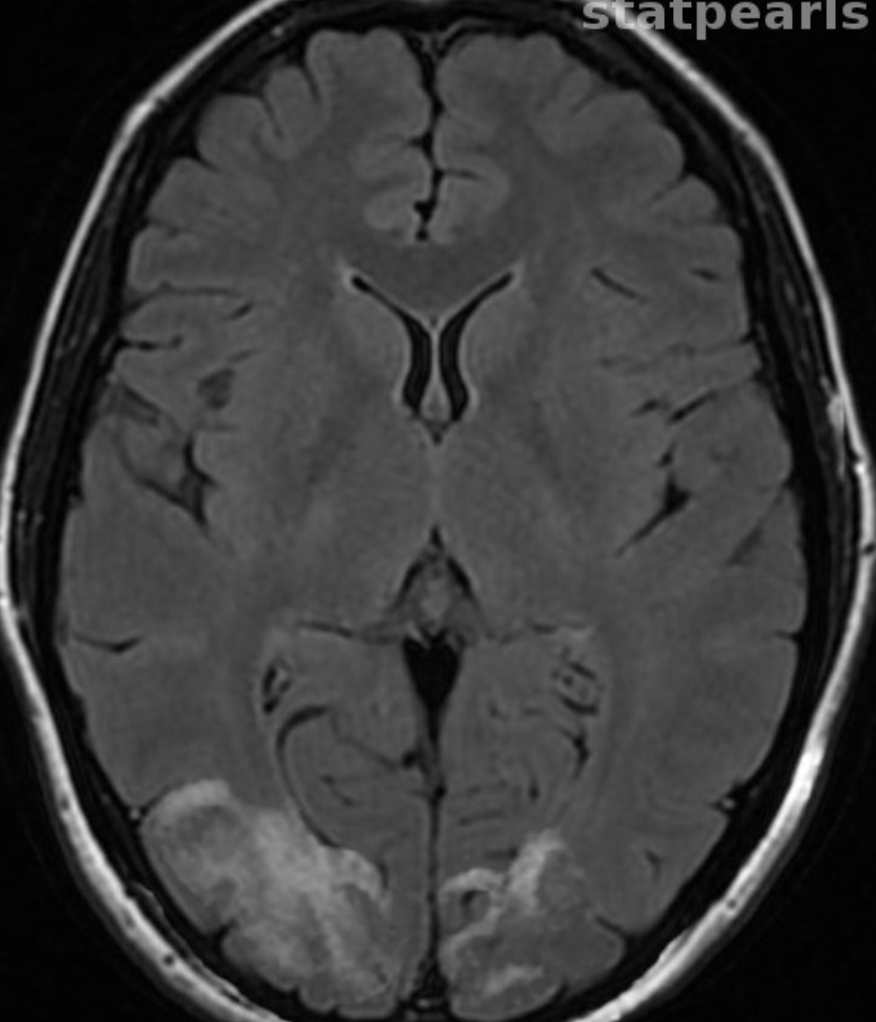

What vein is thrombosed, leading to the outcome below?

Bilateral internal cerebral veins or the vein of galen